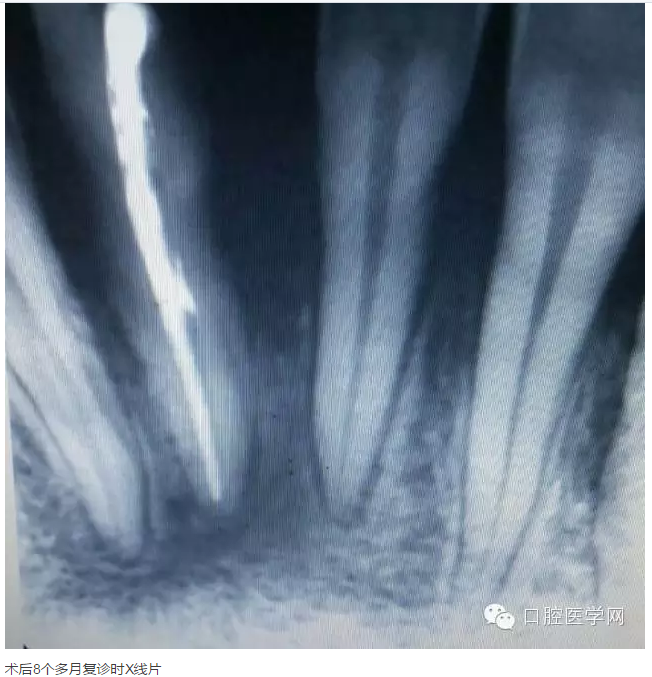

下面是一例 今年年初治療的下前牙根尖囊腫病例,患者因故未能按時(shí)復(fù)診,最近才來。